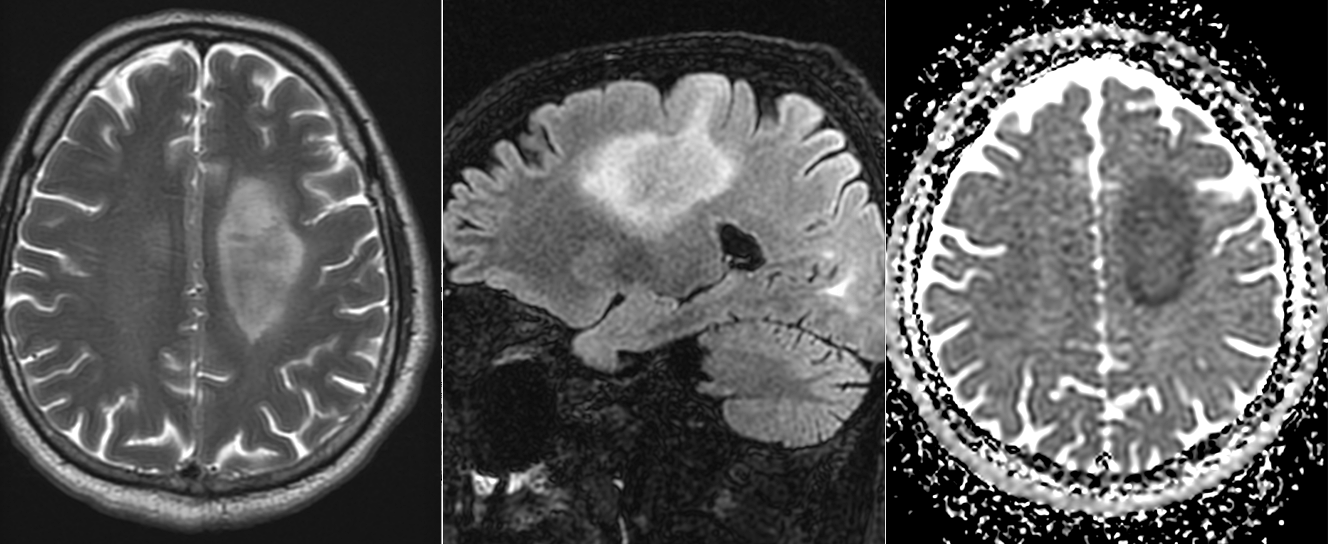

IRM cerebral cu substanță de contrast – metoda de elecție. Limfoamele sunt leziuni cu hipersemnal T2-FLAIR și hiposemnal T1, imprecis delimitate, cu contrast intens, adesea periventriculare si cu aspect caracteristic de difuzie (ADC). Poate mima glioblastomul sau metastazele cerebrale.

Limfoamele cerebrale apar frecvent în emisferele cerebrale, ganglionii bazali, corpul calos, talamus și periventricular.